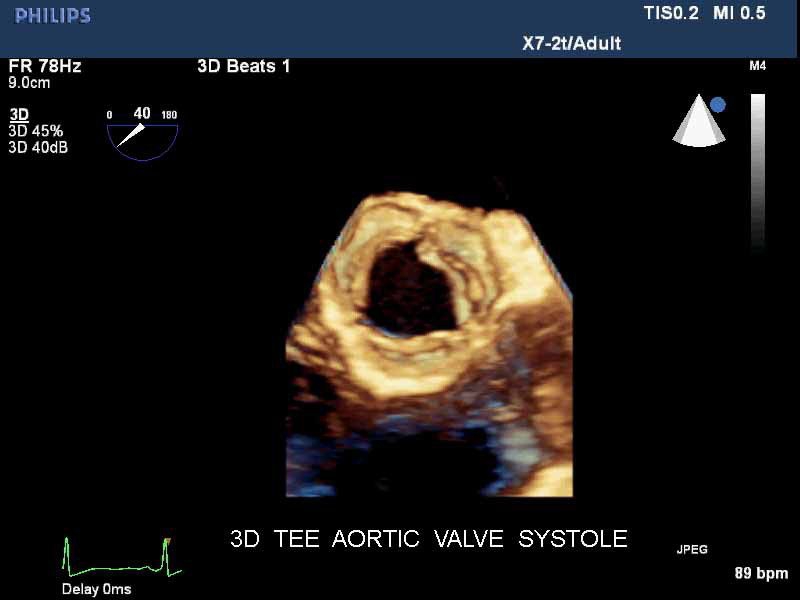

• Live 3D TEE: Эта функция позволяет проводить чреспищеводную эхокардиографию в режиме реального времени, что позволяет оценить механические сокращения сердца с точностью, необходимой для оценки результатов хирургического вмешательства.

• Чреспищеводный УЗИ датчик Philips Х7-2T